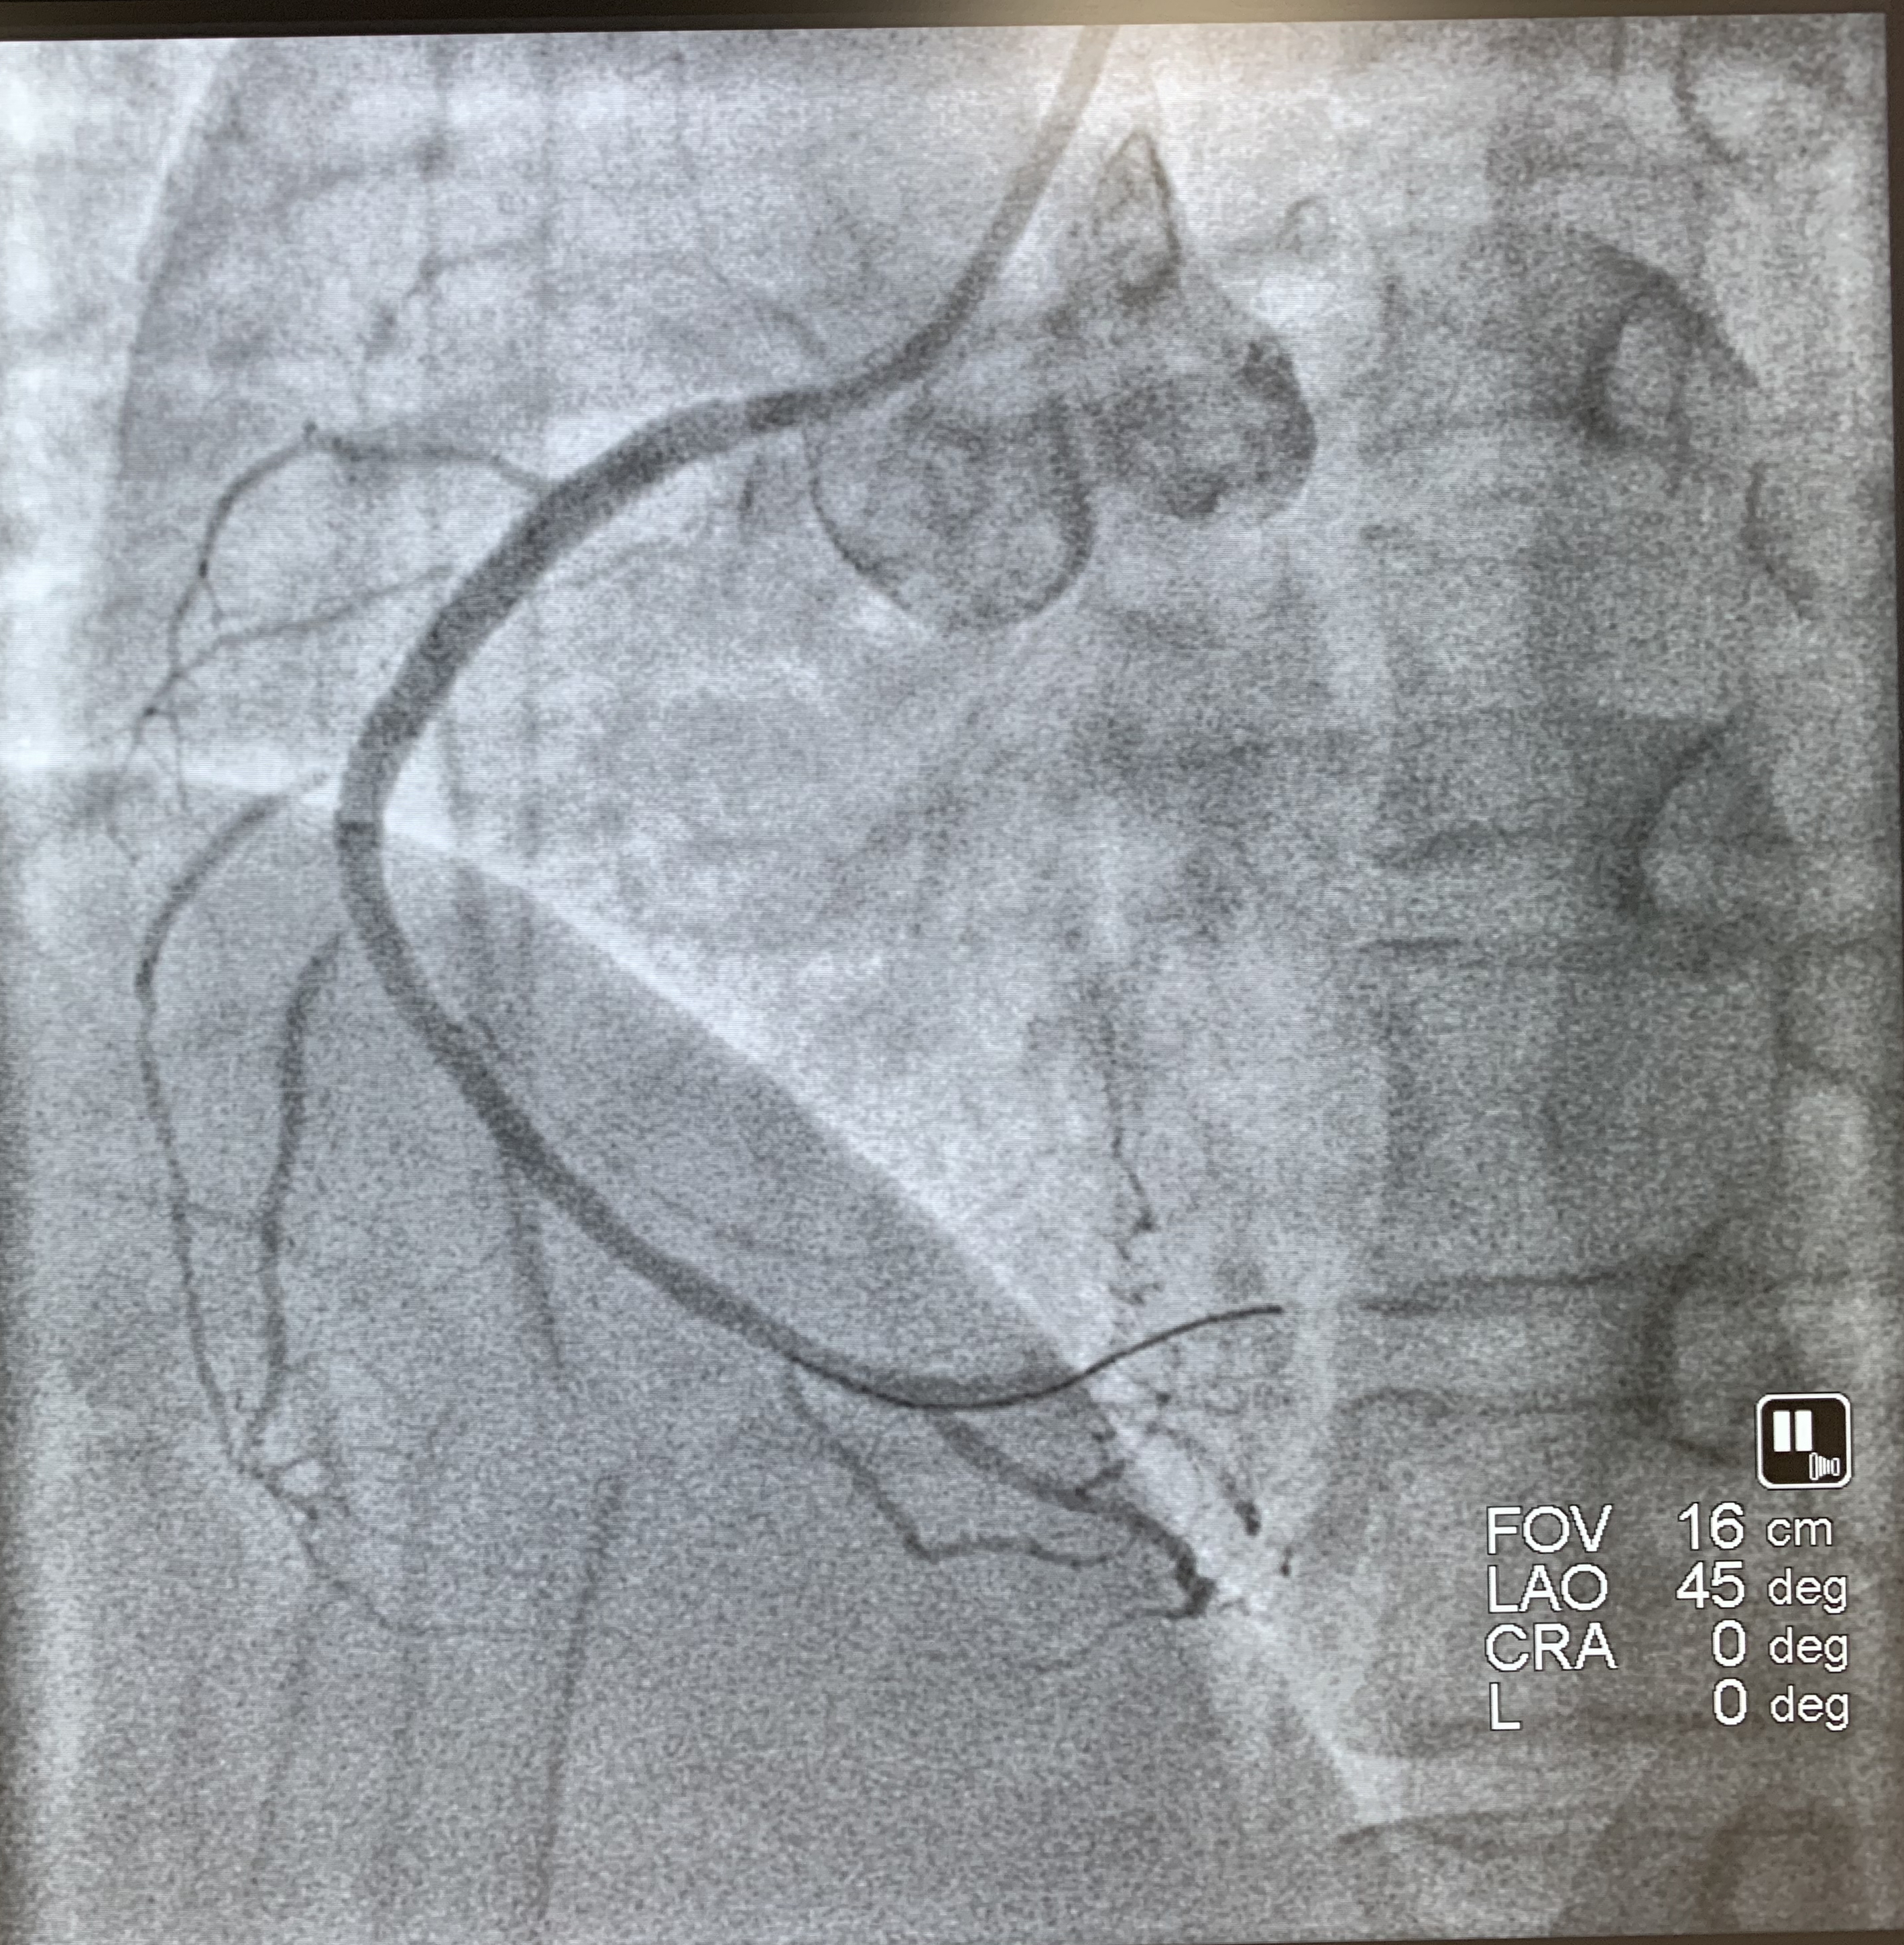

术后

马王堆院区急救。经过心电图等相关检查,迅速明确诊断其为急性心肌梗死,需立即进行急诊介入手术。在冠脉造影检查过程中,医生发现患者的右冠近段以远闭塞。术中,通过用血栓抽吸装置,将冠脉内血栓抽出,然后成功放入一枚支架。术后,患者胸痛不适的感觉明显缓解。